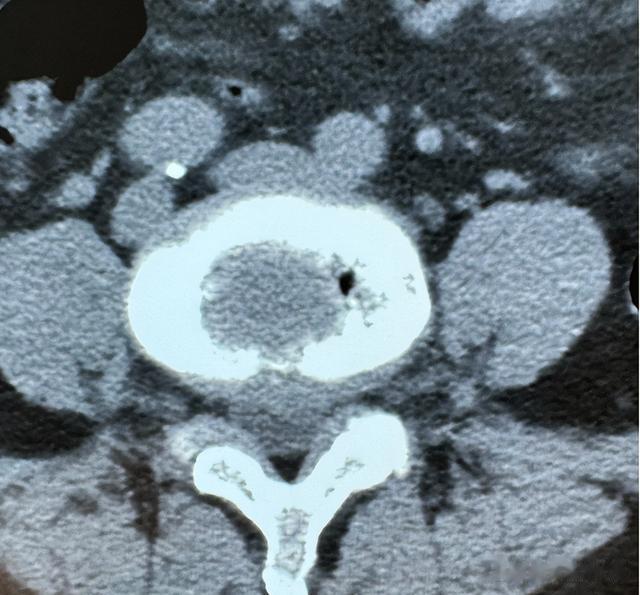

检查报告冰冷地摊在桌上,恶性黑色素瘤晚期,全身多处转移。

更棘手的是老人同时患有肾衰竭,冠心病,高血压,徐赫的心直往下沉,任何一个并发症都可能在手术台上要了老人的命。

最终,一个大胆又精细的方案艰难出炉,在局部麻醉下,同时切除老人面部和脚趾的肿瘤,一次手术解决两个最困扰老人的溃烂源,避免多次手术消耗他本就微弱的体力。

面部巨大的缺损,则采用皮瓣移植——从老人颈部借一块完好的皮肤和皮下组织,旋转覆盖到面部创口上,这将是墨江县医院历史上第一例如此复杂的皮瓣修复手术。